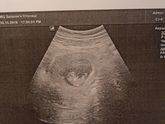

Первое УЗИ23 октября 2019 15:40 Наш врач сказала "О, привет малышь! Добро пожаловать)" Я розрыдалась , а муж подбежал и в панике фоткал все. Он был рад!